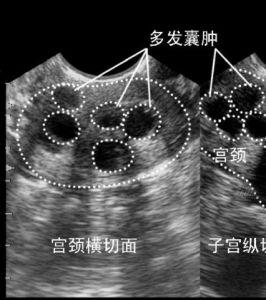

子宫颈腺囊肿是什么

子宫颈腺囊肿是什么,宫颈腺囊肿怎么治疗

宫颈腺囊肿

宫颈腺囊肿怎么治疗

宫颈腺囊肿严重吗

宫颈腺体囊肿

子宫颈囊肿的图片

宫颈腺囊肿图片